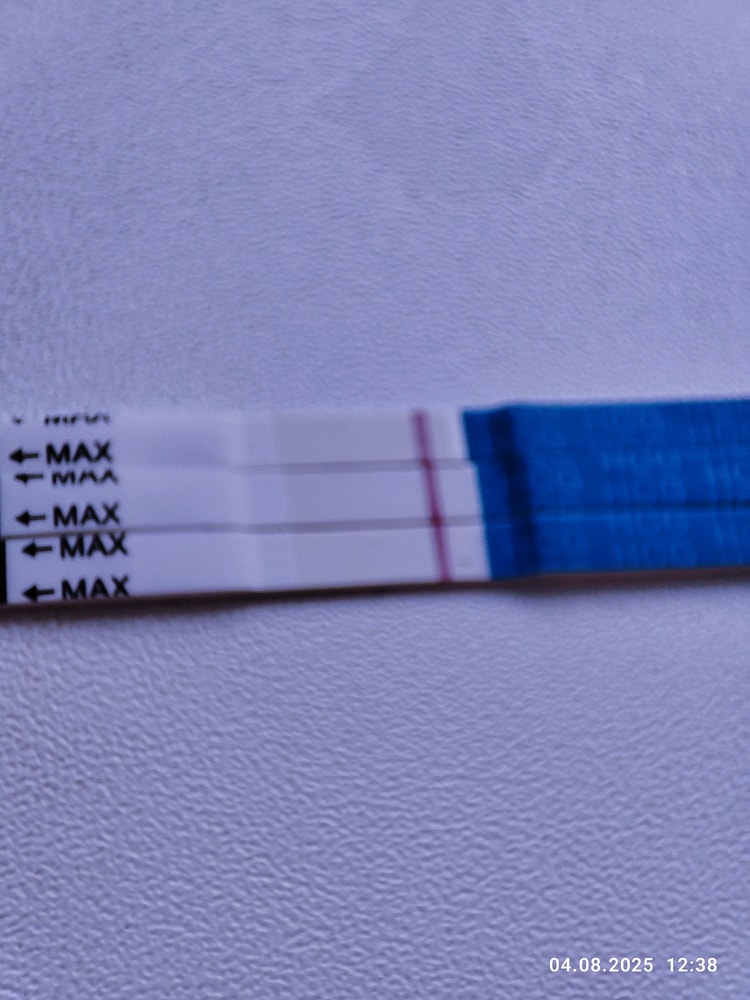

Первые два мама чек

Третий эвик

Мне кажется у эвика что-то есть, но надо повторить однозначтно

Мария Кот, я тоже на эвике вижу, но надо смотреть дальше